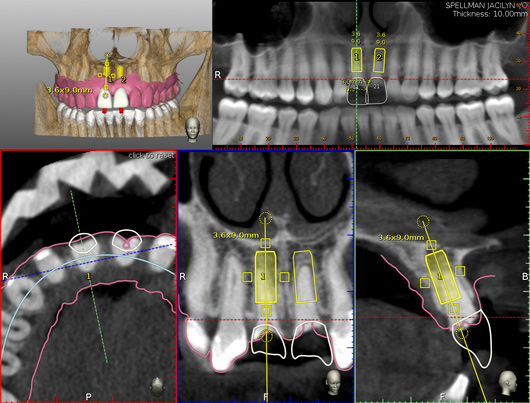

A comprehensive periodontal examination was performed. A thermoplastic retainer and arm were fabricated for the patient with the fiduciary marker (CT marker) attached to the fix plate. Great care was taken regarding the fit of the thermoplastic stent to ensure proper seating. A CBCT scan  (CS 9300, Carestream Dental, carestreamdental.com) of the maxilla was secured, and the DICOM data were registered into the planning software.

The surgery was performed under local-regional anesthesia. The thermoplastic retainer was placed over the remaining teeth and its fit/stability verified. Atraumatic extractions of teeth Nos. 8 and 9 were performed, and intact buccal bone was verified. Osteotomy site preparation and immediate implant placement were performed using the dynamic surgical navigation system. Two 3.6 mm x 9 mm implant fixtures (Astra Tech EV, Dentsply Sirona, dentsplysirona.com) were placed. SmartPegs (Osstell, osstell.com) were attached to the implants to show the trajectory of the fixture positioning. After implant placement, anorganic bovine bone matrix (Bio-Oss®, Geistlich Pharma, geistlich-na.com) was used to graft the implant alveolus "gap," and healing abutments were placed (Figure 9 and Figure 10). The patient was provided with an interim removable appliance for tooth replacement.

A post-placement CBCT scan was secured and compared to the preoperative CBCT plan using software inherent to the dynamic navigation system (Figure 11). Accuracy results from this case (preoperative plan compared to post-implant placement) were as follows: entry point deviation was 0.13 mm for tooth position No. 8 and 0.41 mm for No. 9; angle discrepancy was 4.3 degrees for No. 8 and 6.76 degrees for No. 9; implant apex depth deviation was 1.10 mm for No. 8 and 1.37 mm for No. 9.

Fig 4. Planning software is shown. STL file of the maxillary arch has been imported from optical scanning and matched to regional anatomy for soft-tissue visualization. The aluminum fiduciary of the CT marker can be observed in the axial view. Virtual teeth have been constructed for Nos. 8 and 9, and the case has been planned for prosthetically directed implant placement on a dynamic navigation platform.

Figure 4

Fig 11. Pre- and post-placement CBCT scan matched with DICOM data and accuracy evaluation for site No. 8. Yellow outlines of implant represent the planned implant position, while red outlines show the actual implant position outcome.

Figure 11